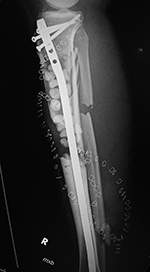

43 year-old man with comminuted right tibia and fibula fractures as well as extensive bone loss and soft tissue injury. A tibial intramedullary nail with proximal and distal locking screws is present as well as multiple rounded bony allografts. There are also large skin staples.